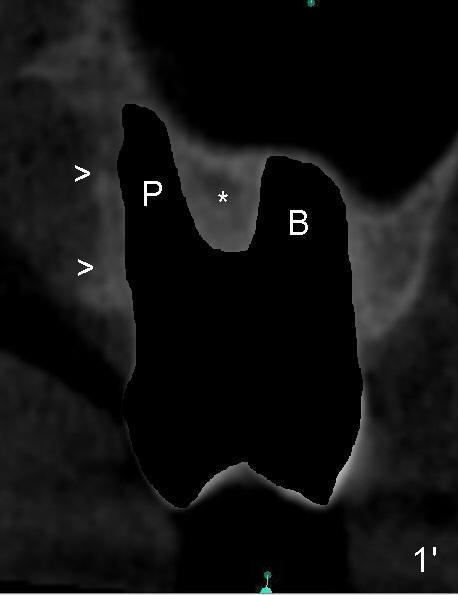

The upper 2nd molar have 3 roots with limited furcation. The buccal ones may be fused (Fig.1 (CT coronal section),2 (sagittal)). After extraction, there are 2 sockets (Fig.1'). When 3 roots are fused, there is a single large socket.

When the buccal roots are fused, there are 3 potential sites for immediate implant (Fig.1'): septum (*), buccal (B) and palatal (P) sockets. Septal placement (6.9x8 mm bone level implant) is the most ideal for restoration (Fig.3). The length of the implant can be increased (10 mm) with sinus lift so that the base of the implant between the buccal and palatal apices in height (Fig.4). Primary stability is derived mainly from the implant body engagement into the septum (Fig.5 coronal section through the septum). If bone density in the septum is high, a small implant may be appropriate (Fig.6,7: 6.4x8 mm). The large implant (6.9 mm) is chosen so that amount of bone graft to be used (Fig.8 red circles) is less.